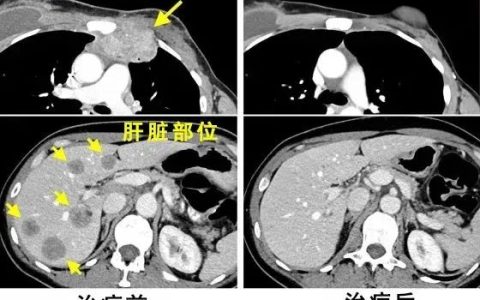

44岁的王先生经过体检,发现右肺脏层胸膜表面之下(肺的内部),存在两枚磨玻璃结节,其中较大者直径有7.6mm,医生建议随访。

王先生为此走访了很多专家医生,医生建议除了定期复查外,需提高自身免疫力。王先生通过朋友推荐使用了一个疗程的免疫细胞应用。治疗几个月后,王先生再次复查,很神奇,肺结节不见了。